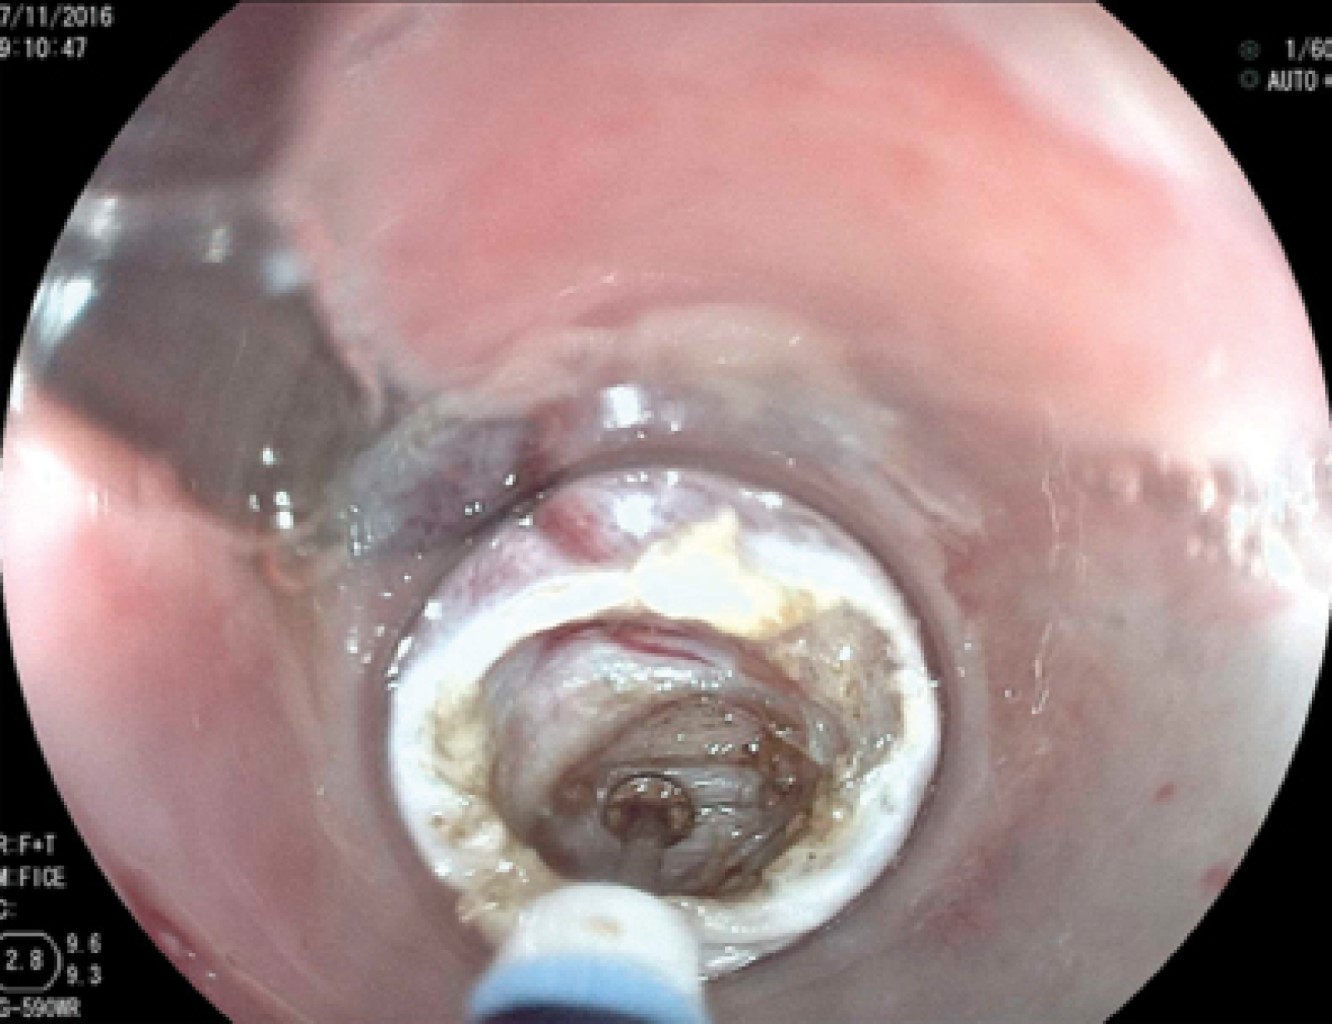

En los primeros 10 pacientes una vez identificada la luz del esófago, se introdujo una guía metálica a la cavidad gástrica y sobre ésta un dilatador de Savary Gilliard de 7 mm o 21 Fr, el cual llega hasta el estómago y se deja en ese sitio. Lo anterior delimita adecuadamente la luz del divertículo y del esófago (Figura 2). En el extremo distal del tubo de inserción del endoscopio se coloca un capuchón plástico transparente (MBL 6-1 Cook Endoscopy) que se utiliza como espaciador, lo que permite identificar el septum del músculo cricofaríngeo. En los primeros 10 casos se utilizó un videogastroscopio Olympus modelo GIF-H140 y procesador de imagen CV-140 Olympus (Olympus Optical Co., Tokio, Japón) de 9.8 mm de diámetro, la unidad electroquirúrgica Olympus UES-40 SurgMaster, y como disector un cuchillo aguja (Needle Knife, Cook Endoscopy, Winston-Salem, NC), se hace un corte en el borde de la luz esofágica en la parte media del septum y hacia la luz del divertículo. Se realiza primero el corte de la mucosa exponiendo las fibras musculares del cricofaríngeo (Figura 3), el corte se profundiza hasta completar la sección de las fibras transversales del esfínter cricofaríngeo, sin necesariamente llegar al fondo del divertículo (Figura 4), lo que permite la aproximación de los bordes de la incisión en la mucosa con clips metálicos evitando la perforación y riesgo de sangrado (Figura 5). A los cuatro pacientes restantes se les aplicó la técnica de POEM (miotomía endoscópica peroral), infiltrando la submucosa con solución fisiológica y azul de metileno para levantar la mucosa, posteriormente, se corta la mucosa con el hidrodisector HybridKnife, tipo T-type marca ERBE que es un instrumento multifuncional que combina tecnología electroquirúrgica e hidrodisección en un solo instrumento con el cual se realiza un levantamiento de la mucosa y la creación de un túnel submucoso, seccionando sólo las fibras musculares transversales y finalmente cerrando la entrada del túnel con clips endoscópicos. En estos pacientes se utilizó un videogastroscopio Fujinon, procesador de imágenes Fujifilm Processor VP-4450HD, unidad electroquirúrgica ERBE VIO 200 D y el HybridKnife de ERBE, T-type (marcas registradas) utilizando corriente de corte y coagulación pura (50 W). Por último se retira el dilatador de Savary Gilliard y posterior al procedimiento se efectuó un trago de material hidrosoluble para descartar fugas. A todos los pacientes se les administró una dosis única de antibiótico al inicio del procedimiento y fueron manejados de forma ambulatoria en domicilio iniciando con dieta líquida a las cuatro horas.

Figura 3